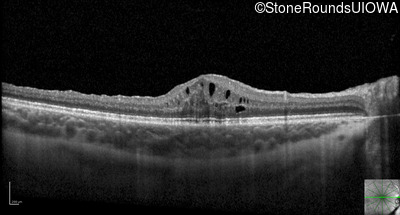

Optical Coherence Tomography - Left - 20/32 sc

Exemplar / OCT Stack